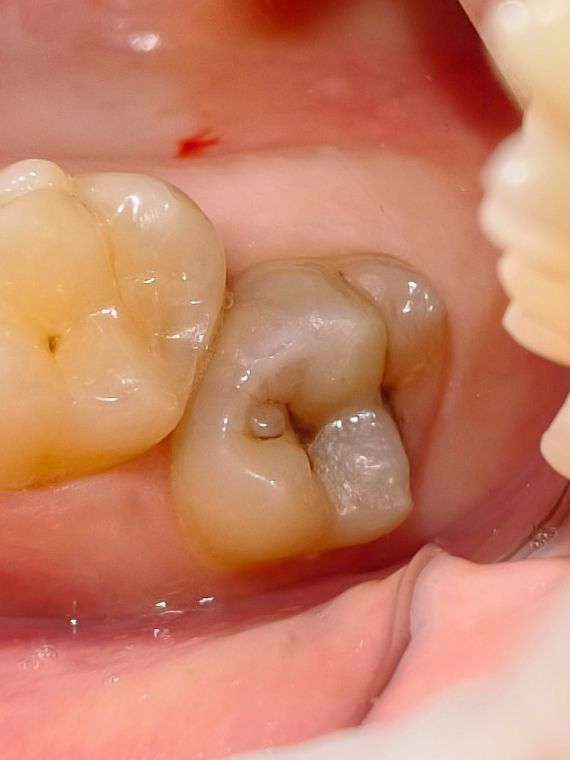

как выглядит зубной кариес на жевательном зубе

На фото представлен глубокий кариес на жевательном зубе

Глубокий кариес на жевательной поверхности легко определяется врачом при осмотре, зуб изменен в цвете с светло желтого на сероватый, можно обнаружить полости темного цвета в которых застревает стоматологический зонд.